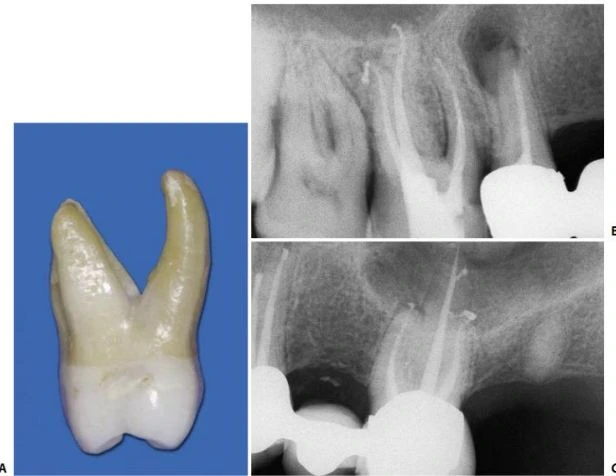

Về mặt giải phẫu học, răng cối nhỏ thứ nhất trên có thể có hình dạng hoàn toàn khác. Ống tủy cong hình lưỡi lê ở 1/3 chóp chân răng là một dạng điển hình. Hiếm khi tìm thấy một ống tủy đơn, hình elip trong một chân răng; thường gặp hai ống tủy giao nhau ở 1/3 giữa với hai lỗ chóp trong một chân răng (38%) hoặc hai ống tủy (thường cùng chiều dài) ở trong hai chân răng riêng biệt (60%). Hiếm hơn nữa có thể thấy ba chân răng với ba ống tủy và những lỗ chóp riêng biệt, chiếm 6% theo Carns và Skidmore , và 5% theo những tác giả khác. Trong những trường hợp này, RCN có hình dạng như răng cối lớn. Một ống tủy rộng hơn ở phía trong và hai ống nhỏ hơn ở phía ngoài, một ở phía gần và một ở phía xa (hình 11.46). Điều trị nội nha tốt hay không phụ thuộc vào việc tạo xoang tủy có đúng hay không: răng cối nhỏ trên với ba ống tủy thì cần tạo một xoang tủy có hình dạng chữ “T” với sự mở rộng theo chiều gần xa ở phần ngoài của xoang truyền thống. Sự thay đổi này cho phép tạo một đường vào tốt cho cả hai ống tủy ngoài. Nếu ba chân răng phân kỳ, ta có thể thấy được trên phim X-quang trước điều trị. Nếu ba chân răng chụm hoặc chồng lên nhau (hình 11.47A), ta có thể biết được trong lúc điều trị. Nha sĩ có thể nghi ngờ có hai ống tủy ngoài không chỉ nhờ vào sự hiện diện của 2 miệng ống tủy (thường không nhận ra hai miệng ống tủy riêng biệt), mà còn nhờ vào hướng của cây trâm thăm dò khi nó đi vào một trong hai ống tủy, hoặc hình dung trên phim X-quang thấy hình ảnh dị dạng nhưng những đường nét chung của chân răng vẫn bình thường [ví dụ: hoàn toàn nằm về phía gần (hình11.47 B)], ta có thể nghi ngờ còn một ống tủy ngoài thứ hai nữa mà hướng của nó nằm về phía xa hơn so với ống thứ nhất (hình 11.47 C, D).

So sánh với răng cối lớn thứ nhất hàm trên, nó hơi nhỏ hơn, kích thước gần xa hẹp hơn, và tỉ lệ có ống gần trong ít hơn (hình 11.73). Kulid và Peters nhận thấy 96.1% răng cối lớn thứ nhất hàm trên có ống gần trong và 93.7% ở răng cối lớn thứ hai hàm trên. Đôi khi nó có ba chân chụm vào nhau. Nó có thể chỉ có hai ống tủy, một ống ngoài và một ống trong trong một chân, hoặc hai ống tủy trong hai chân (hình 11.74); nó có thể có một ống tủy đơn rộng và hướng thẳng từ sàn tủy đến chóp (hình 11.75). Hiếm khi răng cối lớn trên có hình dáng giải phẫu phức tạp hơn, với hai ống trong trong một chân răng (hình 11.76) hoặc trong hai chân răng riêng biệt (hình 11.77).

Hình 11.77. Răng cối lớn thứ hai hàm trên với hai ống trong ở hai chân răng. A. Phim trước điều trị. B. Xoang tủy. C. Phim trong lúc điều trị. D. Phim sau điều trị